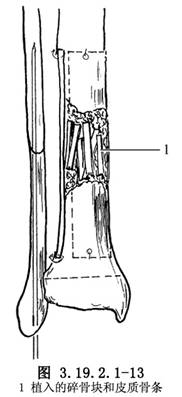

11.4 4.植骨

在脛骨遠、近端的外側和後側,用骨刀鑿一薄層皮質,上端達骨近側斷端上5~7.5cm,下端儘可能接近脛骨遠端骨骺板,但不能損傷它。從對側脛骨切取相應大小的骨膜骨瓣兩塊,骨瓣上下端鑽孔,貼附於已準備好的脛骨外側和後側的粗糙面上,以不吸收線縫合固定於脛骨遠、近端(圖3.19.2.1-12)。植骨骨瓣間和假關節處植入松質骨碎骨塊和皮質骨細骨條(圖3.19.2.1-13)。

2.植骨材料以自體骨爲最好,父母骨次之,異體骨較差。除採用雙側貼附植骨外,在骨斷端周圍、假關節處應植入碎骨塊。